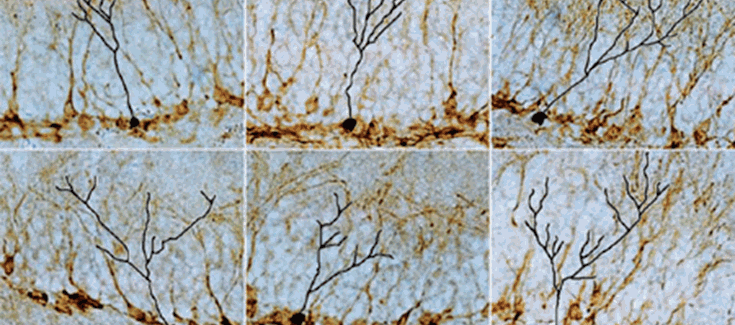

Figura del estudio en la portada de la revista Molecular Psyquiatry

La novedad y calidad del estudio han merecido que una figura del mismo aparezca en la portada del número de la revista, que es la de mayor factor de impacto en psiquiatría.

Portada de la revista con una figura del artículo: